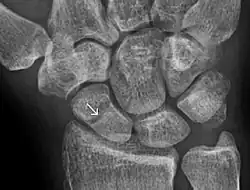

- ^ Jarraya, Mohamed; Hayashi, Daichi; Roemer, Frank W.; Crema, Michel D.; Diaz, Luis; Conlin, Jane; Marra, Monica D.; Jomaah, Nabil; Guermazi, Ali (2013). "Radiographically Occult and Subtle Fractures: A Pictorial Review". Radiology Research and Practice. 2013: 1–10. doi:10.1155/2013/370169. PMC 3613077. PMID 23577253.